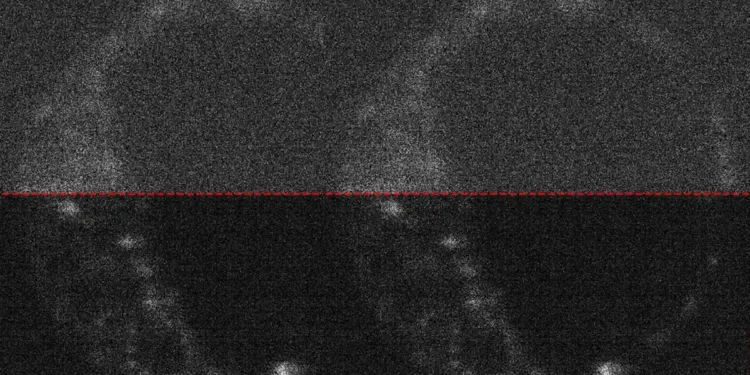

Légende illustration : Image d’un embryon de souris vivant avec et sans capture optimisée. Credit: University of Adelaide